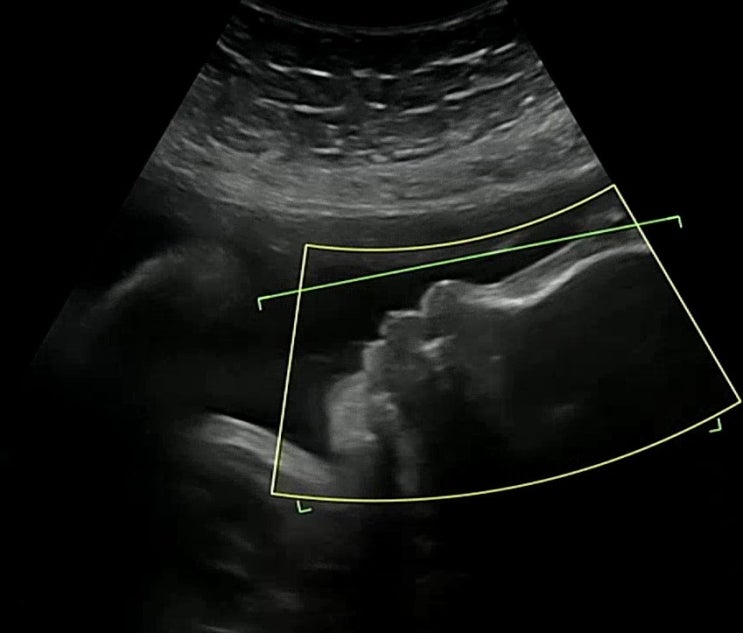

임신 20주~28주 / 비만산모 임당검사 통과, 아기성별 확정, 혼혈아기 입체초음파, 임신중 이사하기

19주 포스팅이 마지막 임신일기였는데 이걸 쓰는 지금은 34주...ㅋㅋㅋㅋ 입니다 임신 후기고 곧 아기를 만...